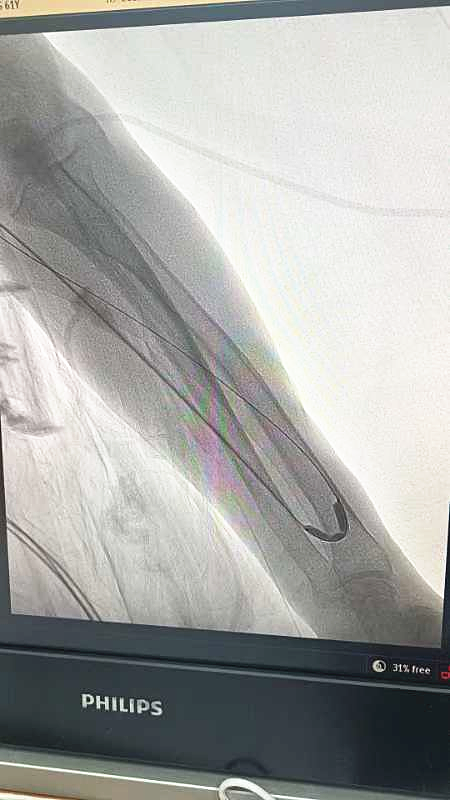

球囊扩张术

扩张中造影